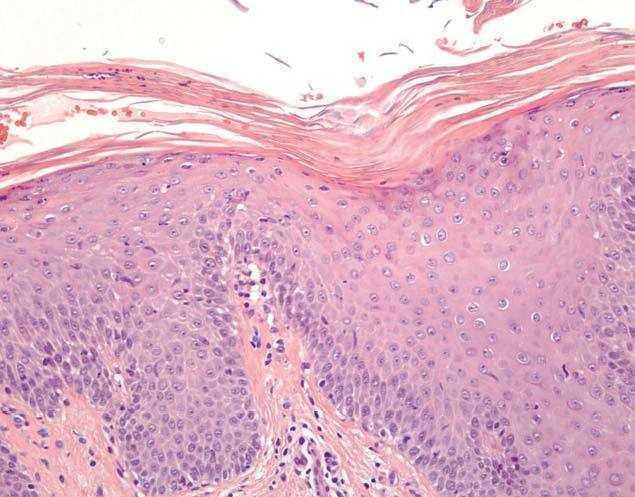

Se trata de un varón de 41 años, sometido a trasplante alogénico de médula ósea por HPN y tratado con tacrolimus y mofetil micofenolato, que acudió por una erupción de una semana de evolución en el territorio correspondiente a los dermatomas torácicos derechos 6 y 7, caracterizada por pápulas eritematoescamosas, asintomáticas, de menos de 1 cm de diámetro. Este cuadro se localizaba en el mismo lugar donde el paciente había presentado, cuatro meses antes, un HZ que había sido tratado con aciclovir por vía intravenosa. Aún eran visibles máculas hiperpigmentadas residuales en esa región junto con las nuevas lesiones eritematoescamosas (fig. 1). Una biopsia cutánea de estas últimas mostró acantosis, hiperqueratosis y paraqueratosis alternante, con aislados microabscesos de neutrófilos (fig. 2). La dermis papilar estaba edematosa con capilares dilatados. No existía evidencia de cambios citopáticos herpéticos. En dicha biopsia, la reacción en cadena de la polimerasa para el virus varicela zóster (VVZ) no reveló ADN viral.

Figura 2. Hiperplasia epidérmica y acúmulos de neutrófilos en áreas de paraqueratosis (hematoxilina-eosina, 40).